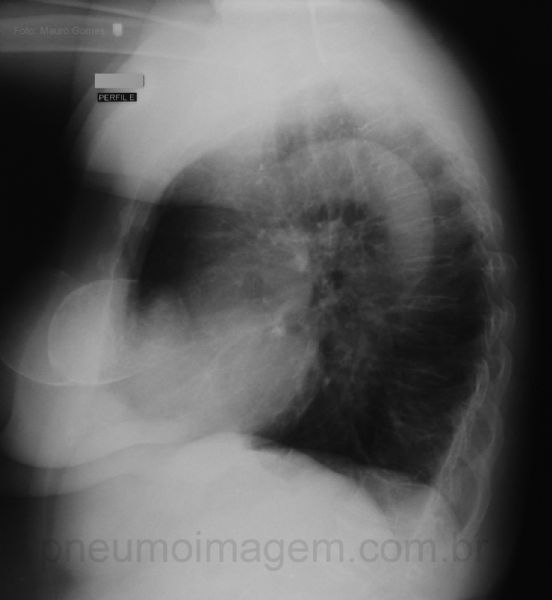

Bilateral and symmetrical areas of greatest density in the anterior chest, which correspond to breast prostheses.

Na incidência em perfil é possível notar que as imagens projetam-se nas partes moles da região anterior do tórax.

In lateral view you can see that the images are projected in the soft tissues of the anterior chest.